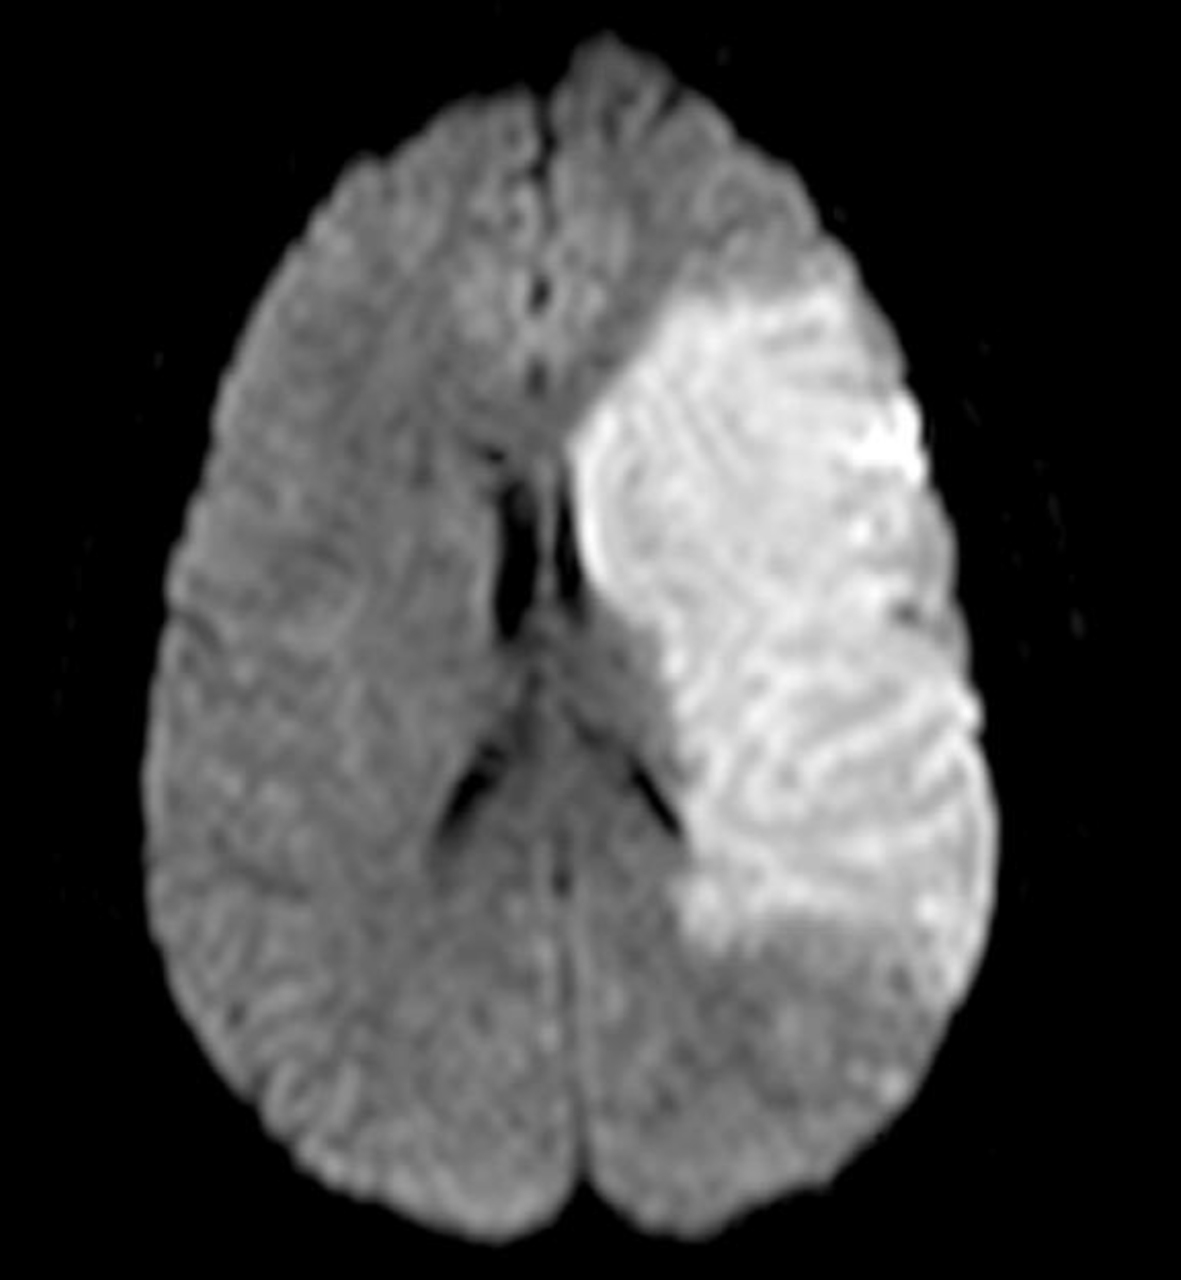

Le seul examen de référence devant ce tableau clinique est l’IRM cérébrale. Il faut la réaliser le plus rapidement pour rester dans les délais de thrombolyse/thrombectomie.

La TDM cérébrale pourrait être envisagée dans un centre éloigné qui ne possède pas d’IRM. Il permettrait de diagnostiquer un AVC hémorragique mais rarement ischémique (signe de la « trop belle artère sylvienne »). Dans ce contexte, nous sommes dans une USINV d’un CHU, l’IRM est l’option numéro 1.